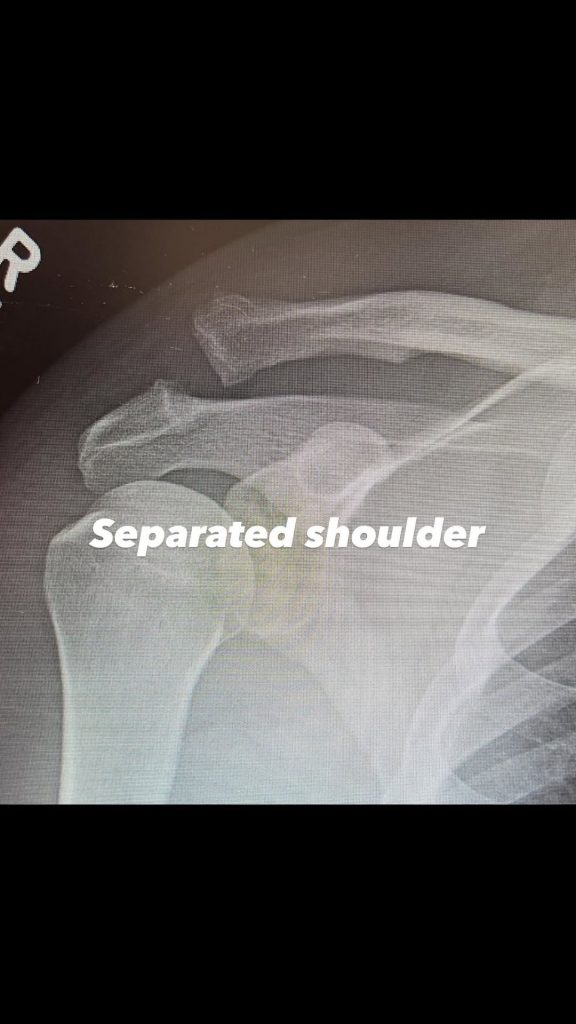

Channing Tatum se ha sometido a una operación tras dislocarse un hombro. En su paso por el Festival de Cine de Sundance, el actor no solo se dedicó a ver películas, sino que también aprovechó para esquiar. Y fue practicando este deporte cuando el protagonista de Foxcatcher o Magic Mike sufrió un percance que le valió una visita al hospital.

Según la cadena de información TMZ, informó que Tatum se lesionó el hombro al caerse mientras esquiaba en Sudance.

El interprete de »Magic Mike» ha compartido vía instagram un post donde se le acostado en la cama con la siguiente descripción: »Otro día más. Otro reto. Este va a ser difícil. Pero bueno. ¡Vamos a por todas!». Donde también por sus historias de Instagram compartío que fue operado en el hombro por un dislocamiento, lo cuál tuvieron que ponerle en su articulación pero ya se encuentra estable.

Hombro dislocado

Hombro, ya operado.

Estás imagenes la compartio el interprete de Gambito en el UCM, donde bromeo sobre el asunto mencionando: ‘‘Hombro atornillado. Yay». El interprete está confirmado para la proxima entrega de UCM »Avengers Dooms Day» que llega en diciembre del 2026, lo cuál le queda un gran camino en su recuperación.